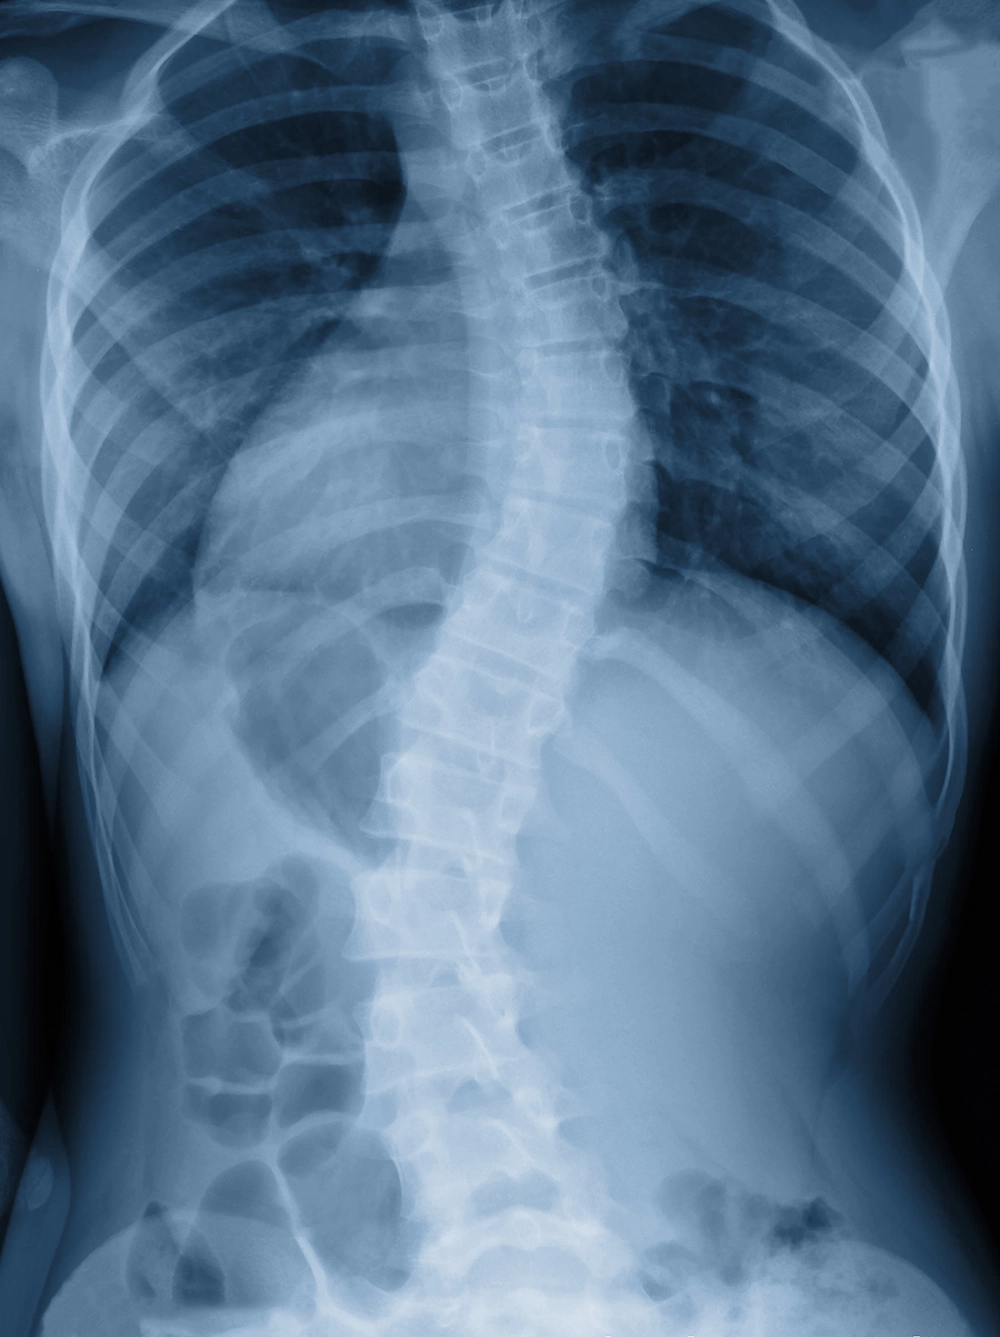

側弯でお悩みの方

脊柱が左右に曲がっている状態が脊柱側弯といいます。